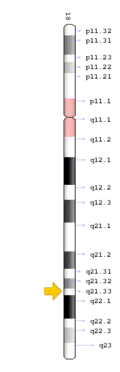

Cytogenetic location of TCIRG1[11]

The TCIRG1 gene is present in chromosome locus 11q13, which encodes for the a3 subunit of vacuolar H+ ATPase (V-ATPase) that is unique to osteoclasts.[12] The a3 subunit is responsible in anchoring the vacuolar proton pump to the ruffled membrane of osteoclasts.[9] The V-ATPase is important in mediating the transport of hydrogen ions into the resorption lacunae, which is a pit on the bone surface enclosed by the osteoclast for bone resorption. The accumulation of ions in the lacuna facilitates the decomposition of hydroxyapatite crystals by creating an acidic environment, resulting in bone resorption.[12]

Cytogenetic location of TNFRSF11A[13]

TNFRSF11A mutation

The TNFRSF11A gene is present in chromosome locus 18q21.33, which encodes for the receptor activator of NF-κB (RANK).[13] RANK is expressed in immature osteoclasts, which facilitates osteoclasts maturation upon binding of RANK ligand (RANKL). Binding of RANK ligand mediates the RANK/RANKL/OPG signalling pathway. The pathway mediates osteoclast differentiation and activation by promoting differentiation of precursors into multinucleated osteoclasts, and activating osteoclasts, thereby contributing to bone resorption and remodelling. Health conditions related to genetic changes in TNFRSF11A includes osteopetrosis, osteolysis, and Paget's disease of bone.[14][15]